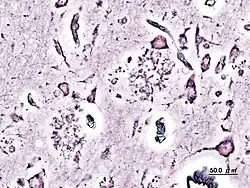

La pratique de la neuropathologie moderne repose essentiellement sur l'examen au microscope de spécimens de tissus nerveux prélevés chirurgicalement chez un patient : il peut s'agir de biopsies cérébrales ou de lésions médullaires détectées par les techniques d'imagerie médicale. Il peut aussi s'agir de biopsies de nerfs périphériques ou de biopsies musculaires. Plus rarement qu'au XIXe siècle, la neuropathologie peut encore avoir recours à l'autopsie pour établir un diagnostic post-mortem.

Les échantillons prélevés sont fixés et inclus dans des blocs de paraffine, puis coupés en fines lamelles au microtome.On utilise largement en première intention les colorations simples comme celles à l'hématoxyline-éosine (HE). Lorsqu'un diagnostic rapide est nécessaire, par exemple au cours d'une intervention chirurgicale sur une tumeur (diagnostic extemporané), les fragments prélevés par le neurochirurgien sont congelés et découpés à l'aide d'un cryotome. On a largement recours aux techniques d'immunofluorescence directe qui utilisent des anticorps dirigés contre différents antigènes tumoraux.

La neuropathologie utilise traditionnellement l'imprégnation métallique pour visualiser les cellules nerveuses en microscopie optique. Les techniques d'imprégnation argentique selon Golgi ou del Río Hortega se sont avérées particulièrement précises.